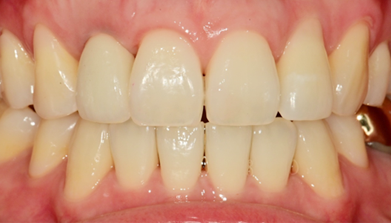

임플란트 최종 결과

BEFORE/AFTER

BEFORE

AFTER